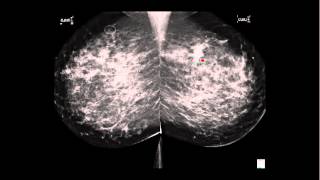

MRI Findings in Metaplastic Breast Cancer New Research!